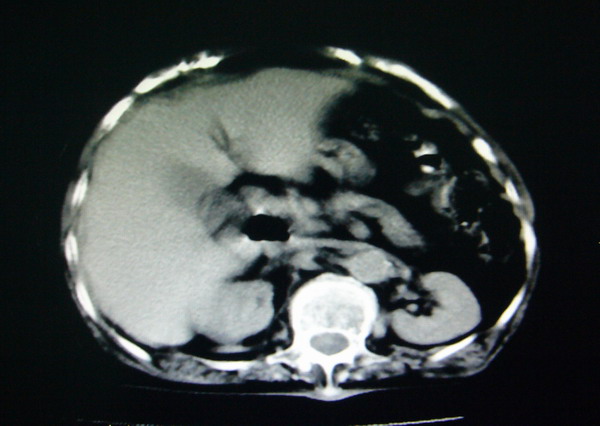

女:83y,转移性右下腹痛2小时,白细胞计数增高。

1.右侧肾盂扩大,肾盏无扩张,考虑:先天性肾盂变异可能性大。

2.胆囊扩张,考虑:胆囊炎。

3.阑尾区域可见以结节样高密度影,结合病史,考虑:阑尾结石,阑尾炎。

右下腹肠系膜增厚,结合病史支持阑尾炎.

右侧壶腹型肾盂可能,建议输路造影或增强

1.右侧肾盂扩大,考虑先天性肾盂变异或肾盂旁囊肿。

2.胆囊扩张,考虑胆囊炎。

3.阑尾区域可见结节样高密度影,结合病史考虑:阑尾结石、阑尾炎。